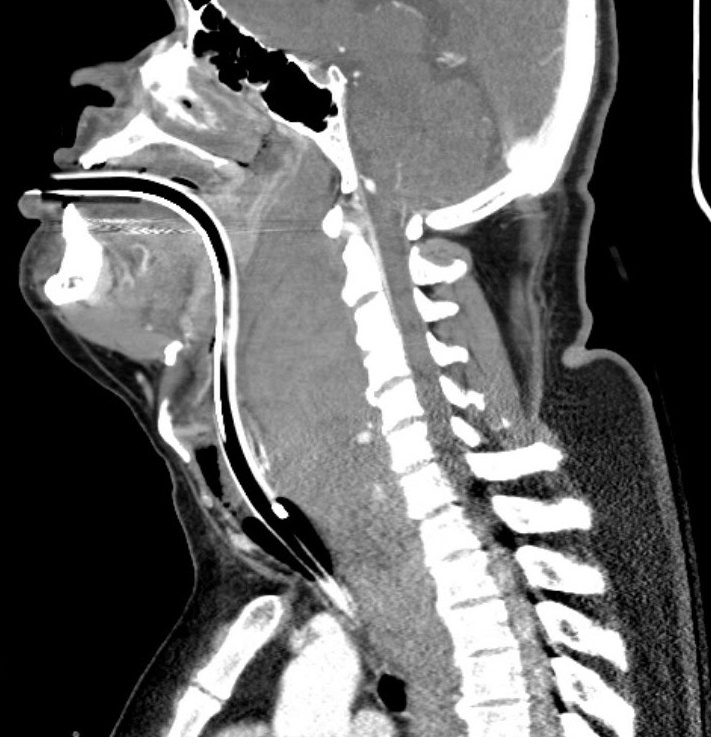

CT scan was deferred due to the exacerbation of airway obstruction in the supine position. X-ray of the neck showed marked prevertebral soft tissue swelling (>7cm) and mass effect indicative of a large hematoma in the retropharyngeal space (Figure 1). An anesthesiology consult led to a discussion of airway management strategies, comparing awake fiberoptic intubation with video laryngoscopy. Given the edematous and narrowed airway, glidescope video laryngoscopy (GVL) was chosen for maneuverability of the mandible. Ketamine 250 mg IV was administered to maintain spontaneous ventilation, with preoxygenation to 100% SpO2 prior to intubation. A laryngeal mask airway and cricothyrotomy kit remained available at bedside.